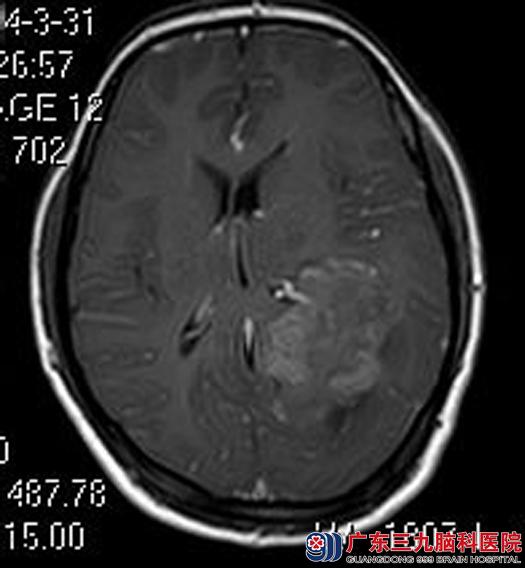

一过性的眼睛发黑竟然是脑肿瘤造成的,小芳和她的家人似信非信地来到广东三九脑科医院,综合神经外科的鲁明主任也考虑脑肿瘤的可能性大,进一步行头颅MR检查,结果提示:左侧侧脑室三角区为主,示一不规则病变,大小约37.3mm×63.7mm×43.0mm。

全麻下行左侧三角区脑膜瘤切除术,术中显微镜下见肿瘤边界清楚,质韧,前至颞叶,后至枕叶,与左侧脑室后角粘连,镜下全切除肿瘤,术后病理证实:过渡型脑膜瘤。